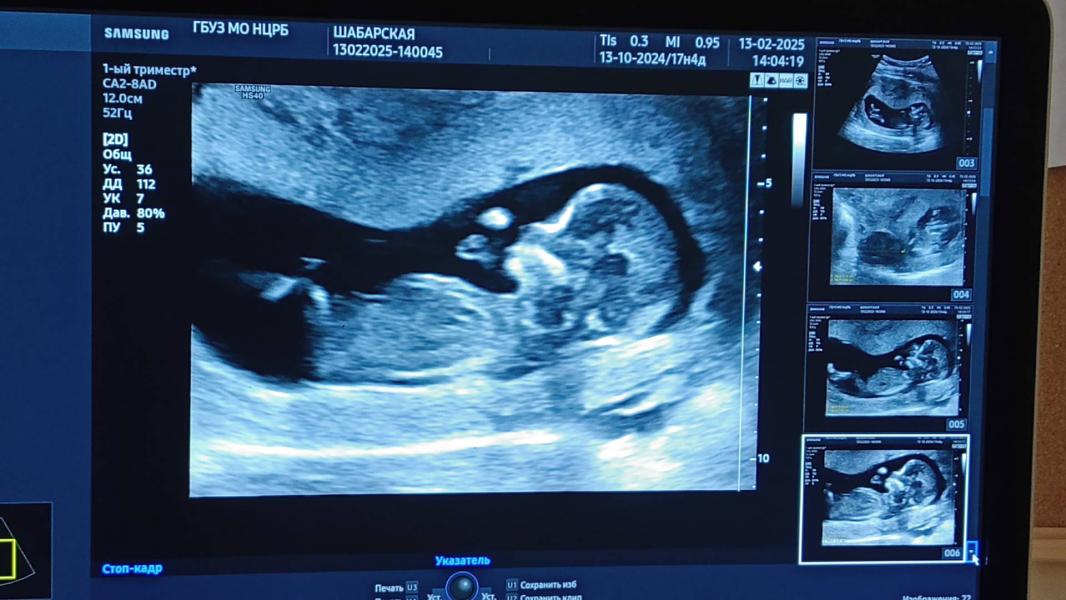

13.02 был первый скрининг( миомка -32 мм). По развитию плода 13,1 неделя, чуть побольше чем я считала.Все хорошо по УЗИ развитие плода по неделям все совпадает все хорошо.можно ли на 13 недели определить пол по узи(у кого совпадало?).Предположили что мальчик сказали во второй скрининг будет точно известно.Не ожидала что второй скрининг будет уже так скоро 1.04.